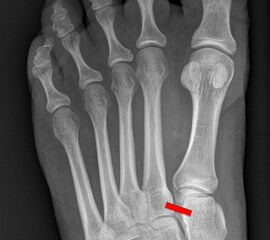

Auf den dp-Aufnahmen sollte der mediale Rand der Metatarsale-2-Basis mit dem medialen Rand des Os cuneiforme intermedium eine homogene Linie ohne Stufenbildung bilden (Abb. 7+8). Außerdem ist auf den Abstand zwischen der Metatarsale-1- und -2-Basis zu achten. Dieser sollte nicht größer als 2 mm bzw. im Vergleich zur Gegenseite nicht mehr als 1 mm erweitert sein. In bis zu 90% der Fälle zeigt sich ein sogenanntes „Fleck sign“ (Abb. 9), ein knöchernes Fragment zwischen der Metararsale-1- und -2-Basis im Sinne eines knöchernen Ausrisses des Lisfranc-Ligaments an der Metatarsale-2-Basis 211936410. Oft liegen zusätzliche Frakturen der Metatarsalebasen oder der Tarsale vor, die ebenfalls identifiziert werden sollten. Bei jeder Mittelfußbasisfraktur sollte umgekehrt an eine Lisfranc-Verletzung gedacht werden.

Zum Lesen der Bildbeschreibung und zur Vollansicht bitte die Bilder anklicken.